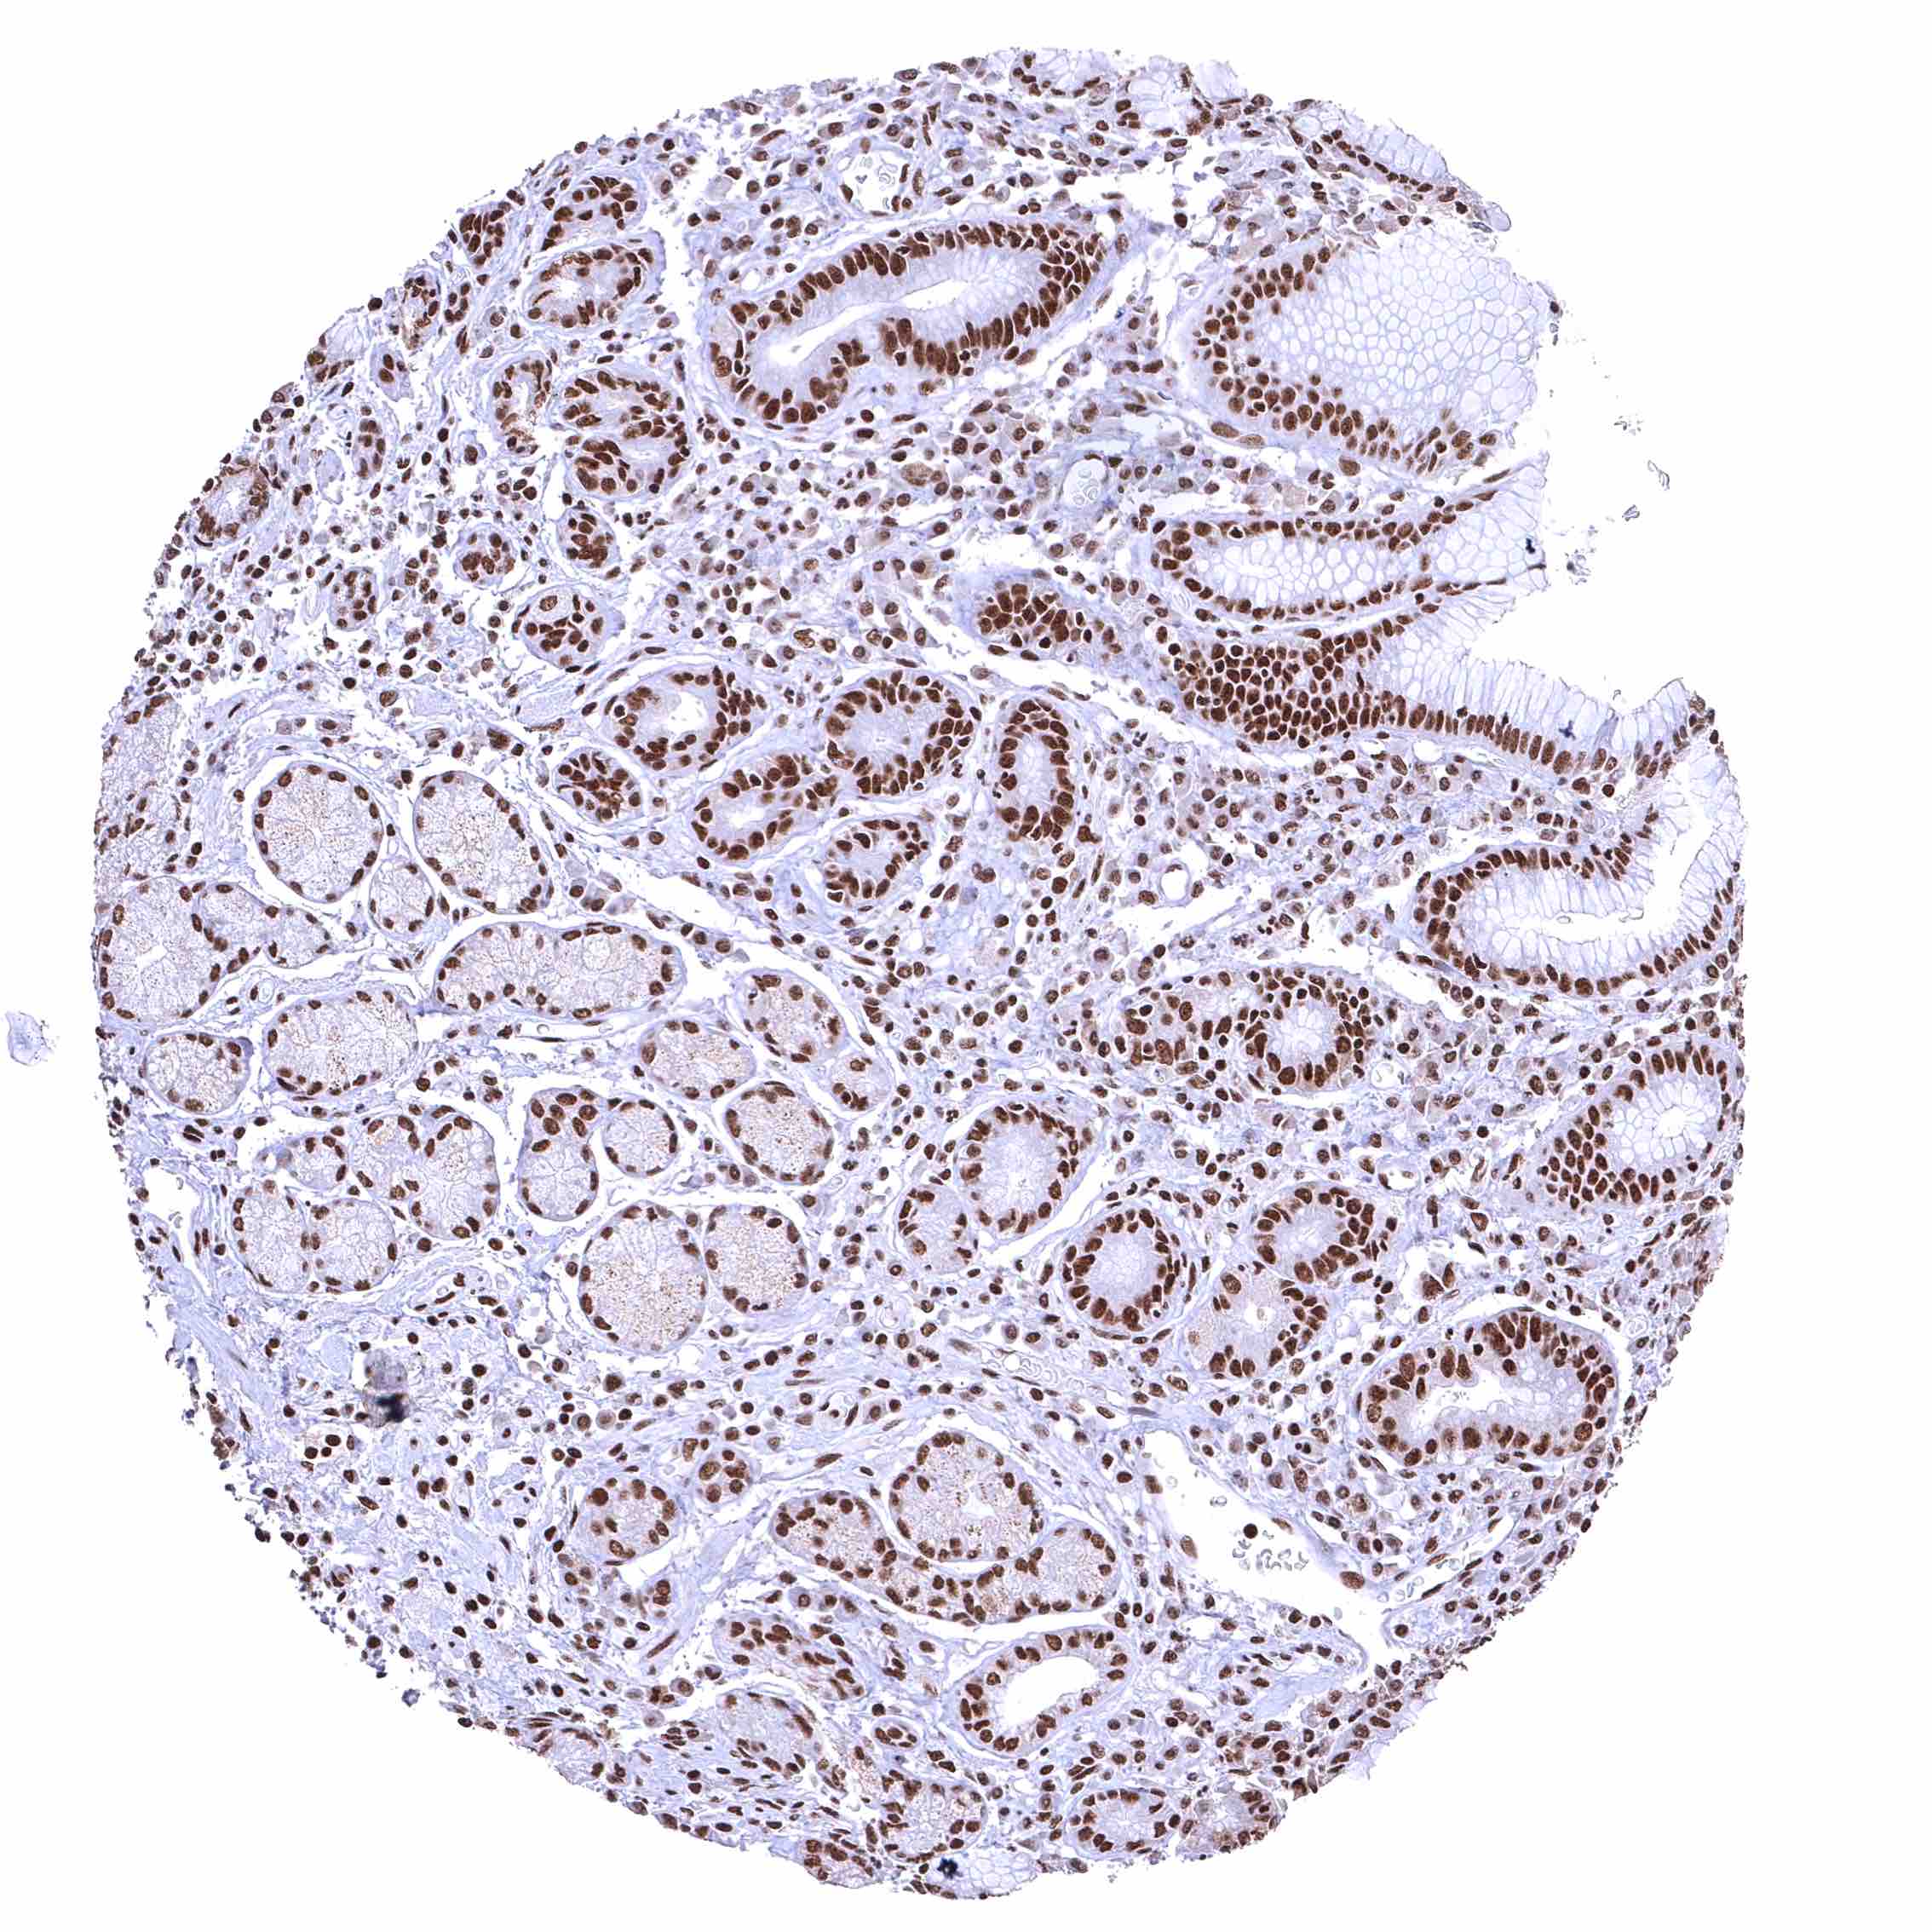

BRD4 antibody [HMV4275] HistoMAX™

Colon descendens, mucosa – Nuclear BRD4 staining of surface epithelial cells is weaker than in crypts.

Rectum, mucosa – Nuclear BRD4 staining of surface epithelial cells is weaker than in crypts.